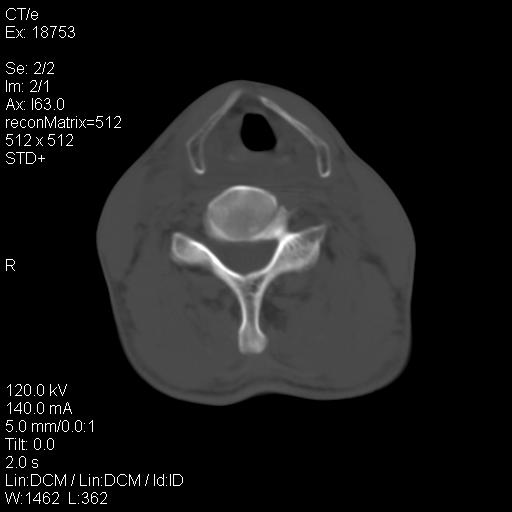

标题: CT21693:男 58岁 右侧咽部疼她2天余 PE:右侧扁桃体肿大 压痛 [打印本页]

标题: CT21693:男 58岁 右侧咽部疼她2天余 PE:右侧扁桃体肿大 压痛

右化脓性扁桃体炎症伴咽后壁脓肿形成.

1 弥漫性肿胀,与周围组织分界清晰,发病急,有明显症状,考虑急性炎症【wbc]

弥漫性肿胀,与周围组织分界不清,发病急,有明显症状,考虑:感染性病变!